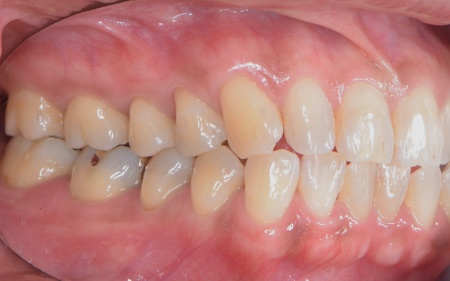

続いて噛み合わせを拝見したところ、前歯がしっかりと噛み合わない開咬(かいこう)という状態です。

この開咬により、本来前歯で分散して受け止めるべき噛む力が、すべて奥歯に集中していることがわかりました。そのため下顎隆起が発生し、また重度歯周病の大きな原因になっていると考えられます。

以上のことから、噛み合わせの問題を根本的に解決しない限り歯周病の治療を行っても再発のリスクが高く、長期的な口腔内の健康維持は困難です。

そのため、歯周病の治療と併せて噛み合わせを改善する必要があると診断しました。